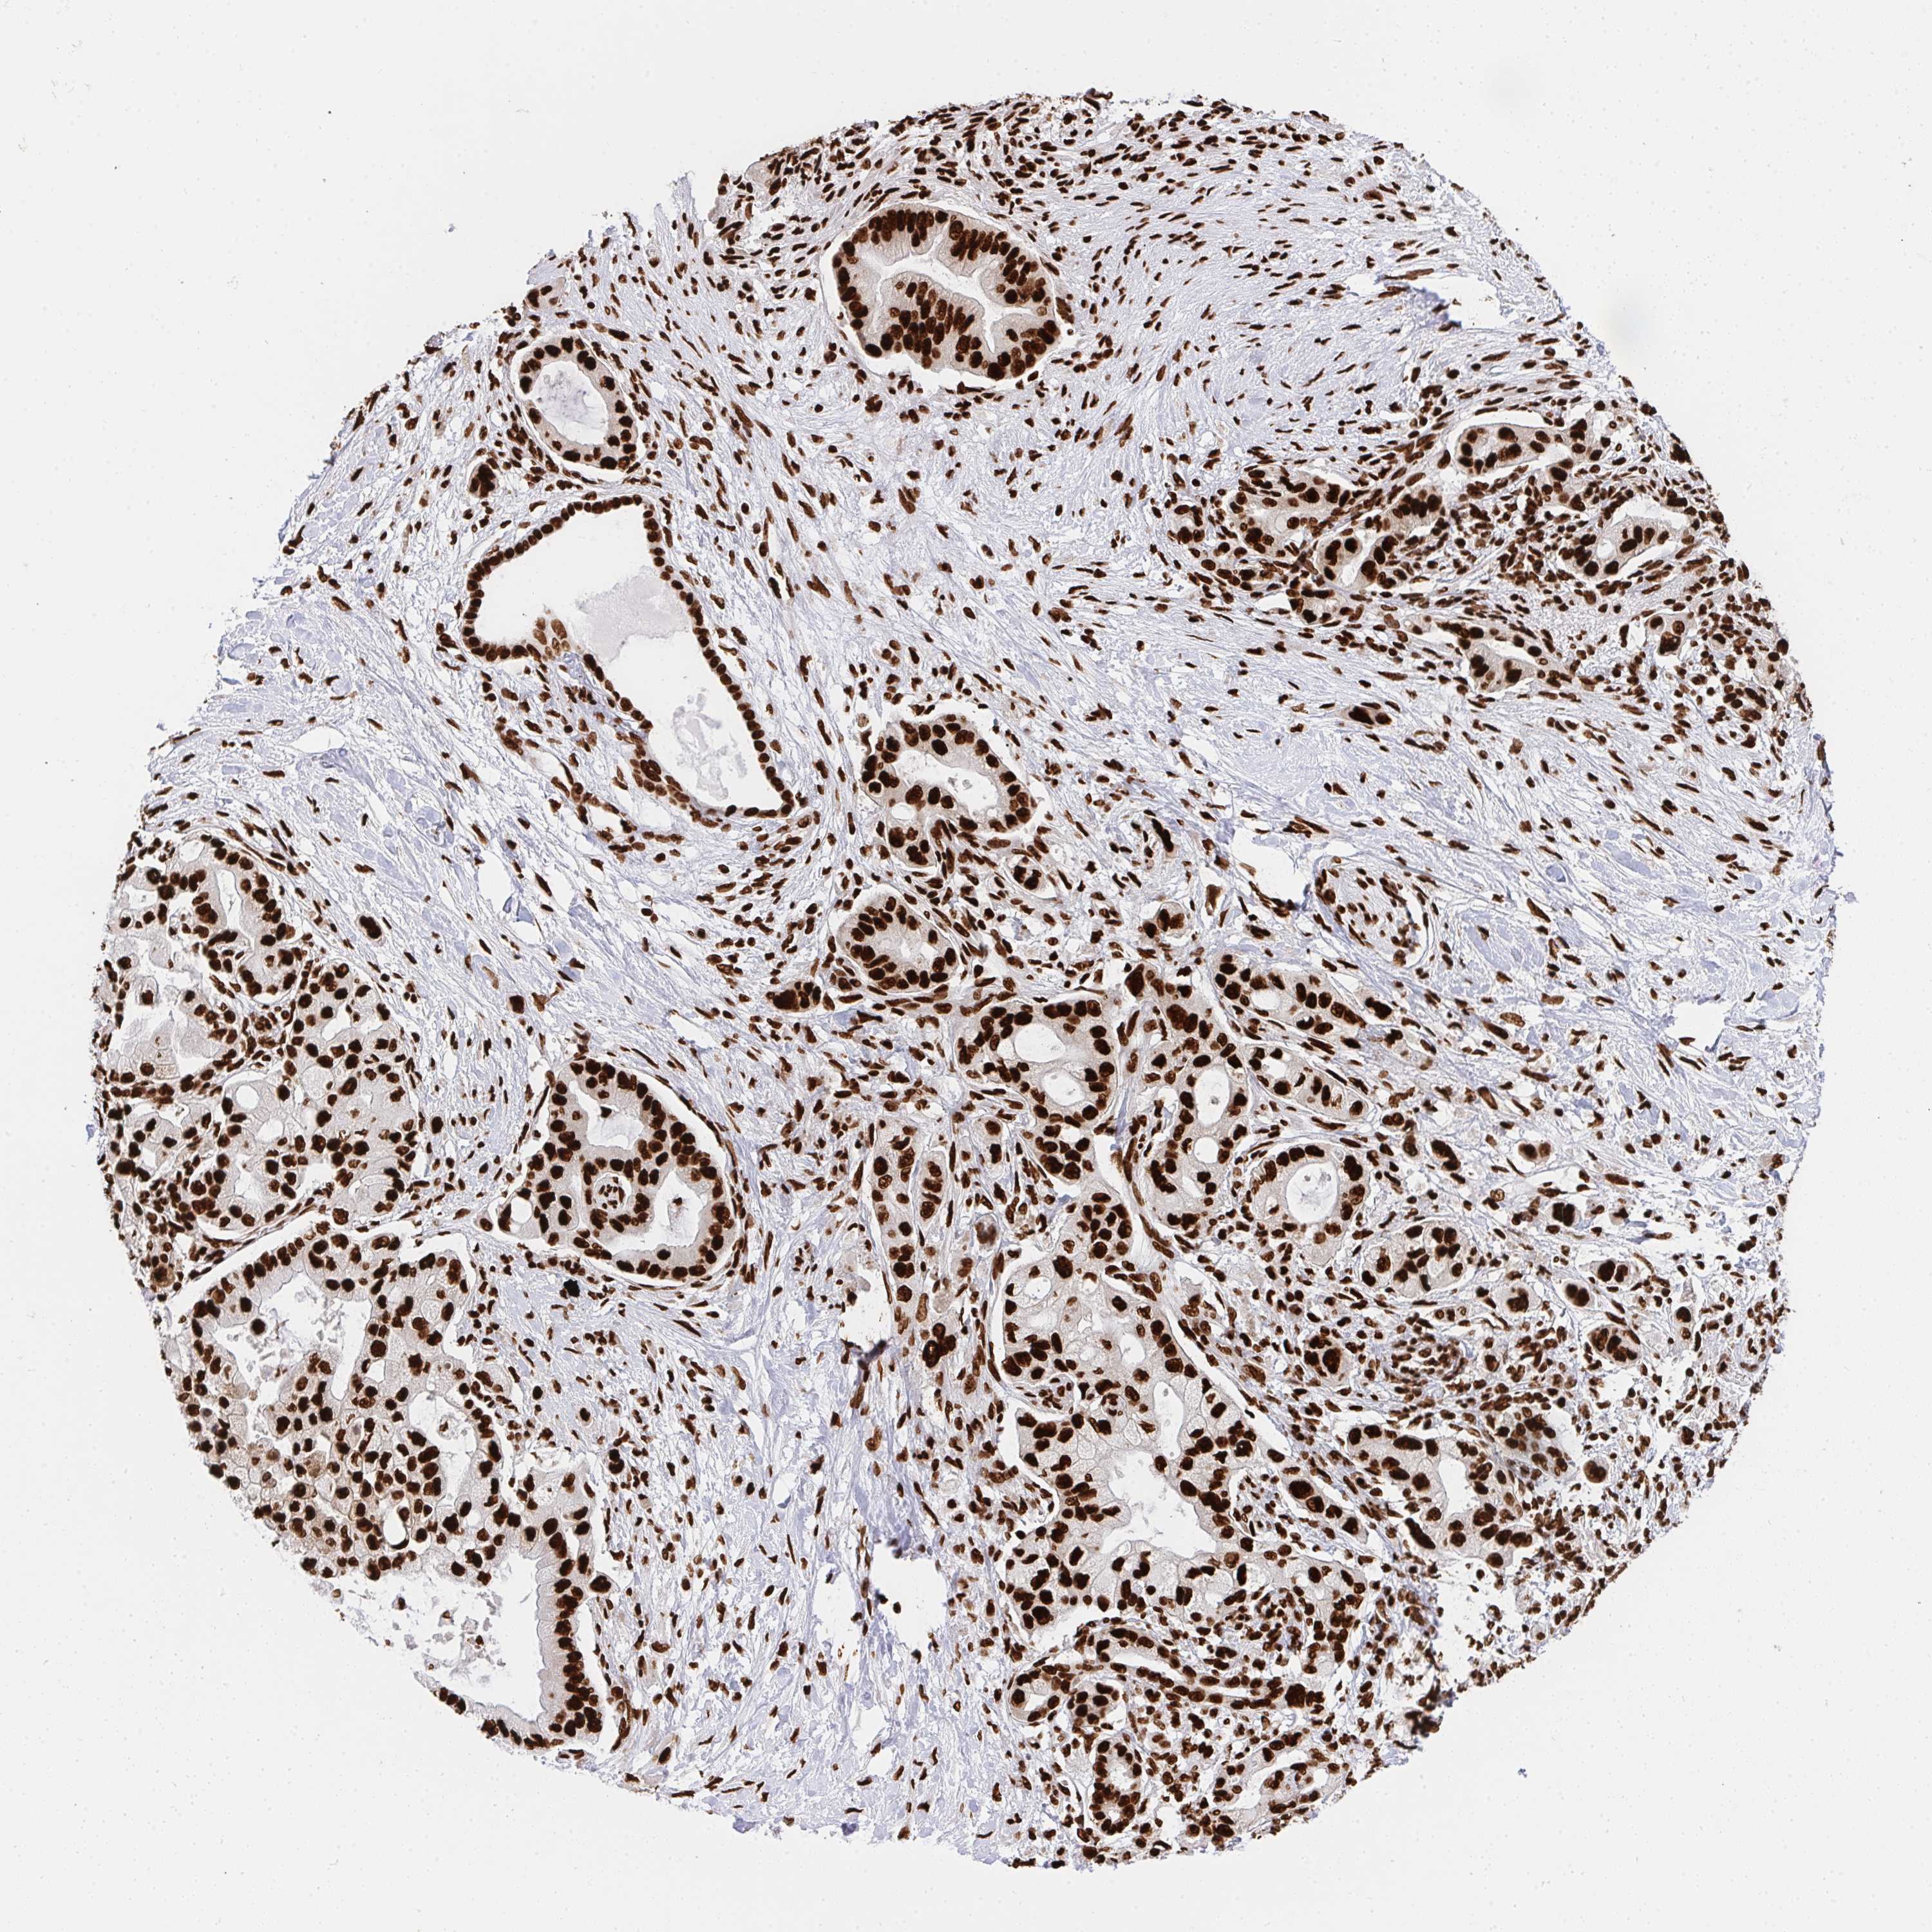

PANCREATIC CANCER - Protein expressioni

A mouse-over function shows sample information and annotation data. Click on an image to view it in a full screen mode. Samples can be filtered based on level of antibody staining by selecting one or several of the following categories: high, medium, low and not detected. The assay and annotation is described here.

Note that samples used for immunohistochemistry by the Human Protein Atlas do not correspond to samples in the TCGA dataset.

Antibody stainingi

Antibody staining in the annotated cell types in the current human tissue is reported as not detected, low, medium, or high, based on conventional immunohistochemistry profiling in selected tissues. This score is based on the combination of the staining intensity and fraction of stained cells.

Each image is clickable and will lead to virtual microscopy that enables deeper exploration of all samples and also displays staining intensity scores, fraction scores and subcellular localization as well as patient and tissue information for each sample.

Antibody HPA051748

Antibody HPA052661

Antibody CAB016326

Staining

High

Medium

Low

Not detected

Intensity

Strong

Moderate

Weak

Negative

Quantity

>75%

75%-25%

<25%

None

Location

Nuclear

Cytoplasmic/membranous

Cytoplasmic/membranous,nuclear

Adenocarcinoma, NOS